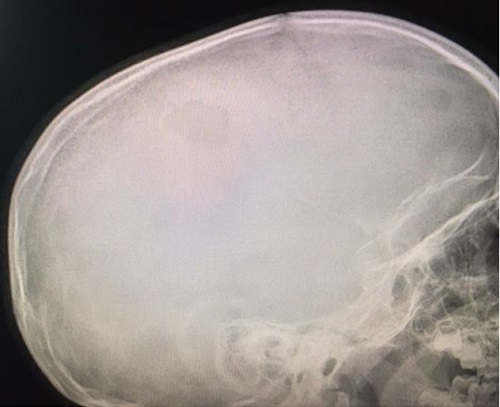

Paciente de 4 años que acude con su madre a consulta por bultoma en cuero cabelludo descubierto de forma casual 7 días antes, sin relación con antecedente traumático y con dolor a la palpación. Desde entonces presenta despertares nocturnos con irritabilidad, que mejoran con analgésicos. Antecedentes familiares y personales sin interés. Desarrollo madurativo normal. Vacunas adecuadas para su edad. No alergias conocidas. El paciente presenta muy buen estado general, apirético y con exploración normal, tanto somática como neurológica, salvo tumoración de consistencia blanda en región parietal izquierda de 2,5-3 cm de diámetro, dolorosa a la palpación. Se deriva al hospital de referencia para pruebas de imagen. La Rx de cráneo muestra una lesión osteolítica en sacabocados, posiblemente compatible con GE (Figura 1). Rx de tórax, serie ósea y ecografía abdominal normales. TAC craneal evidencia los mismos signos (Figura 2). La RMN detecta una lesión única intraósea expansiva parietal izquierda, que atraviesa la tabla ósea externa e interna con mínimo engrosamiento, e hipercaptación de la duramadre subyacente, sugerente de GE como primera posibilidad radiológica. Hemograma y bioquímica dentro de la normalidad.

Figura 1. Radiografía lateral de cráneo